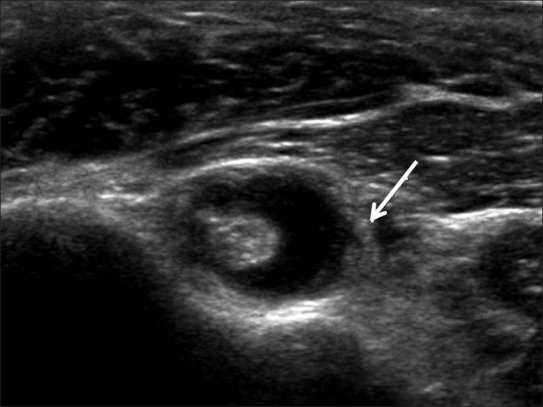

Así es como se verían las alteraciones del bíceps en ecografía:

Ecografía axial del tendón de la porción larga del bíceps, donde se aprecia líquido y engrosamiento sinovial alrededor de su vaina (flecha).

Subluxación medial del tendón de la porción larga del bíceps, visible con la corredera bicipital vacía (flecha), hallazgo sugestivo de inestabilidad del bíceps. LT: troquín.